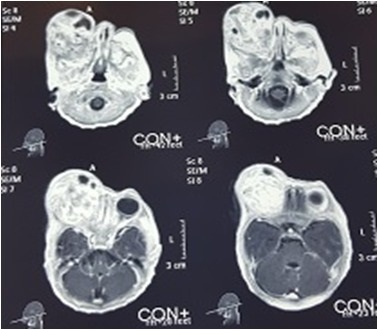

A 9-day-old female neonate presented with massive proptosis of right eye since birth. She was first born child with unremarkable perinatal and family history. On examination, right eye showed extensive proptosis. The eyeball was in the center and surrounded by the tumor (Fig. 1A), making it impossible to distinguish the anatomical boundaries of the globe. There was severe conjunctival chemosis and corneal melting because of exposure keratopathy. Details of anterior and posterior segments were completely obscured. Left eye was unremarkable. B-scan ultrasound of right eye showed calcifications in the vitreous. MRI showed a heterogonous density mass in right orbital cavity, with post-contrast enhancement displacing the globe inferiorly (Fig. 2). Radiological diagnosis was a complex mass with internal hemorrhage or a teratoma. Laboratory tests were within normal ranges.

Figure 2

Axial T1 post contrast MRI: showing a heterogenous mass in right orbit with globe displacement.

Radiological features of benign orbital teratomas include multi loculated cystic mass with focal calcifications and fat. Eyeball is compressed and optic nerve may be displaced. There is distension of orbital walls without their destruction. Ultrasound shows multiple areas of low and high reflectivity in addition to foci of calcification.[9] Retinoblastoma is an important cause intraocular calcification in this age group, so may be considered as a differential diagnosis.[10] Management of congenital orbital teratoma is not straightforward. As tumor is rapidly progressive, salvaging vision is always challenging. Mee et al, were able to prevent useful vision after surgery in an 18-month-old baby with inferior orbital teratoma, as eyeball was not destroyed by the tumor.[11] In our case, irreversible damage was caused by exposure keratopathy and corneal melting thus precluding vision salvage. Early surgical intervention was done. Although vision cannot be preserved in cases like the index case, but prompt surgery prevents further mutilating surgeries like radical exenteration.